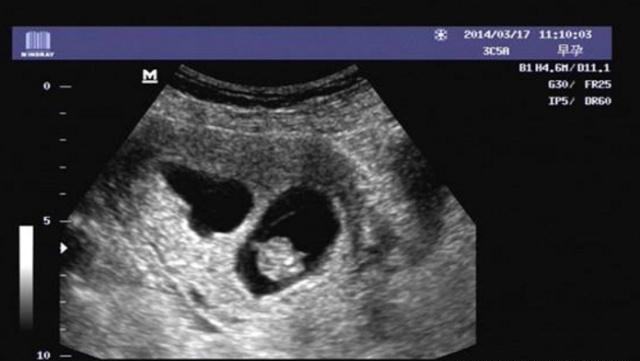

孕囊也叫妊娠囊、胎囊。一般情况下也能在女人子宫内的位置都是比较正常的,只有孕囊没有出现模糊不清或者是太靠后的情况就可以,如果在怀孕后,孕囊在女人子宫的下部形态有些不规则,或者是出现了阴道流血腹痛的情况,就需要及时的就医了。

从B超单上的数据我们可以了解到,如果是偏圆形的运动,通常三个数据会比较接近,那么如果出现了长一点的运动数据单上的一个数据会被另外两个要大一点。通过孕囊的数据来判断宝宝的性别并没有什么科学依据。有些孕妈妈通过看孕囊的数据来得知宝宝的性别,只不过是一种运气罢了。孕期猜测宝宝的性别可以当作是孕期的一种消遣,千万不要太当真了。

怀孕早期就可以看见孕囊,一般情况下月经周期是28~30天,当女性朋友停经35天左右,通过B超检查就可以看到子宫当中的孕囊了,刚怀孕到6周左右的时候,孕囊的直径会达到两厘米左右,怀孕10周左右,孕囊可能会达到五厘米左右。通过孕囊的大小和形状,我们只能够判断女人怀孕的时间,并不能判断胎儿的性别,所以说,不要太认真了。